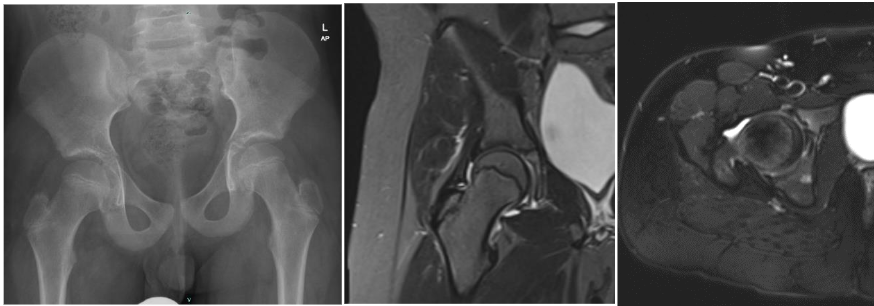

The location of overuse injuries can vary depending on the specific sport and the individual’s biomechanics. This case report discusses a rare instance of femoral head insufficiency fracture in a young gymnast, highlighting the need for awareness and early diagnosis in similar cases.

Diagnosing overuse injuries can be challenging, as they may mimic other conditions. Early recognition and intervention are critical to prevent long-term complications. In this case, the young gymnast presented with hip pain that was initially attributed to overtraining.